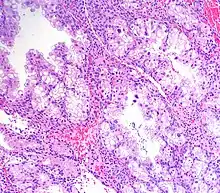

Al microscopio óptico, se observan alteraciones en las glándulas del endometrio en varios focos. Las células, y especialmente los núcleos se ven agrandados. Estos pueden mostrar una cromatina de aspecto vacuolizado o granular, aunque también pueden verse núcleos condensados y compactos (o sea, picnóticos). Se han descrito las siguientes variantes histológicas:[2]